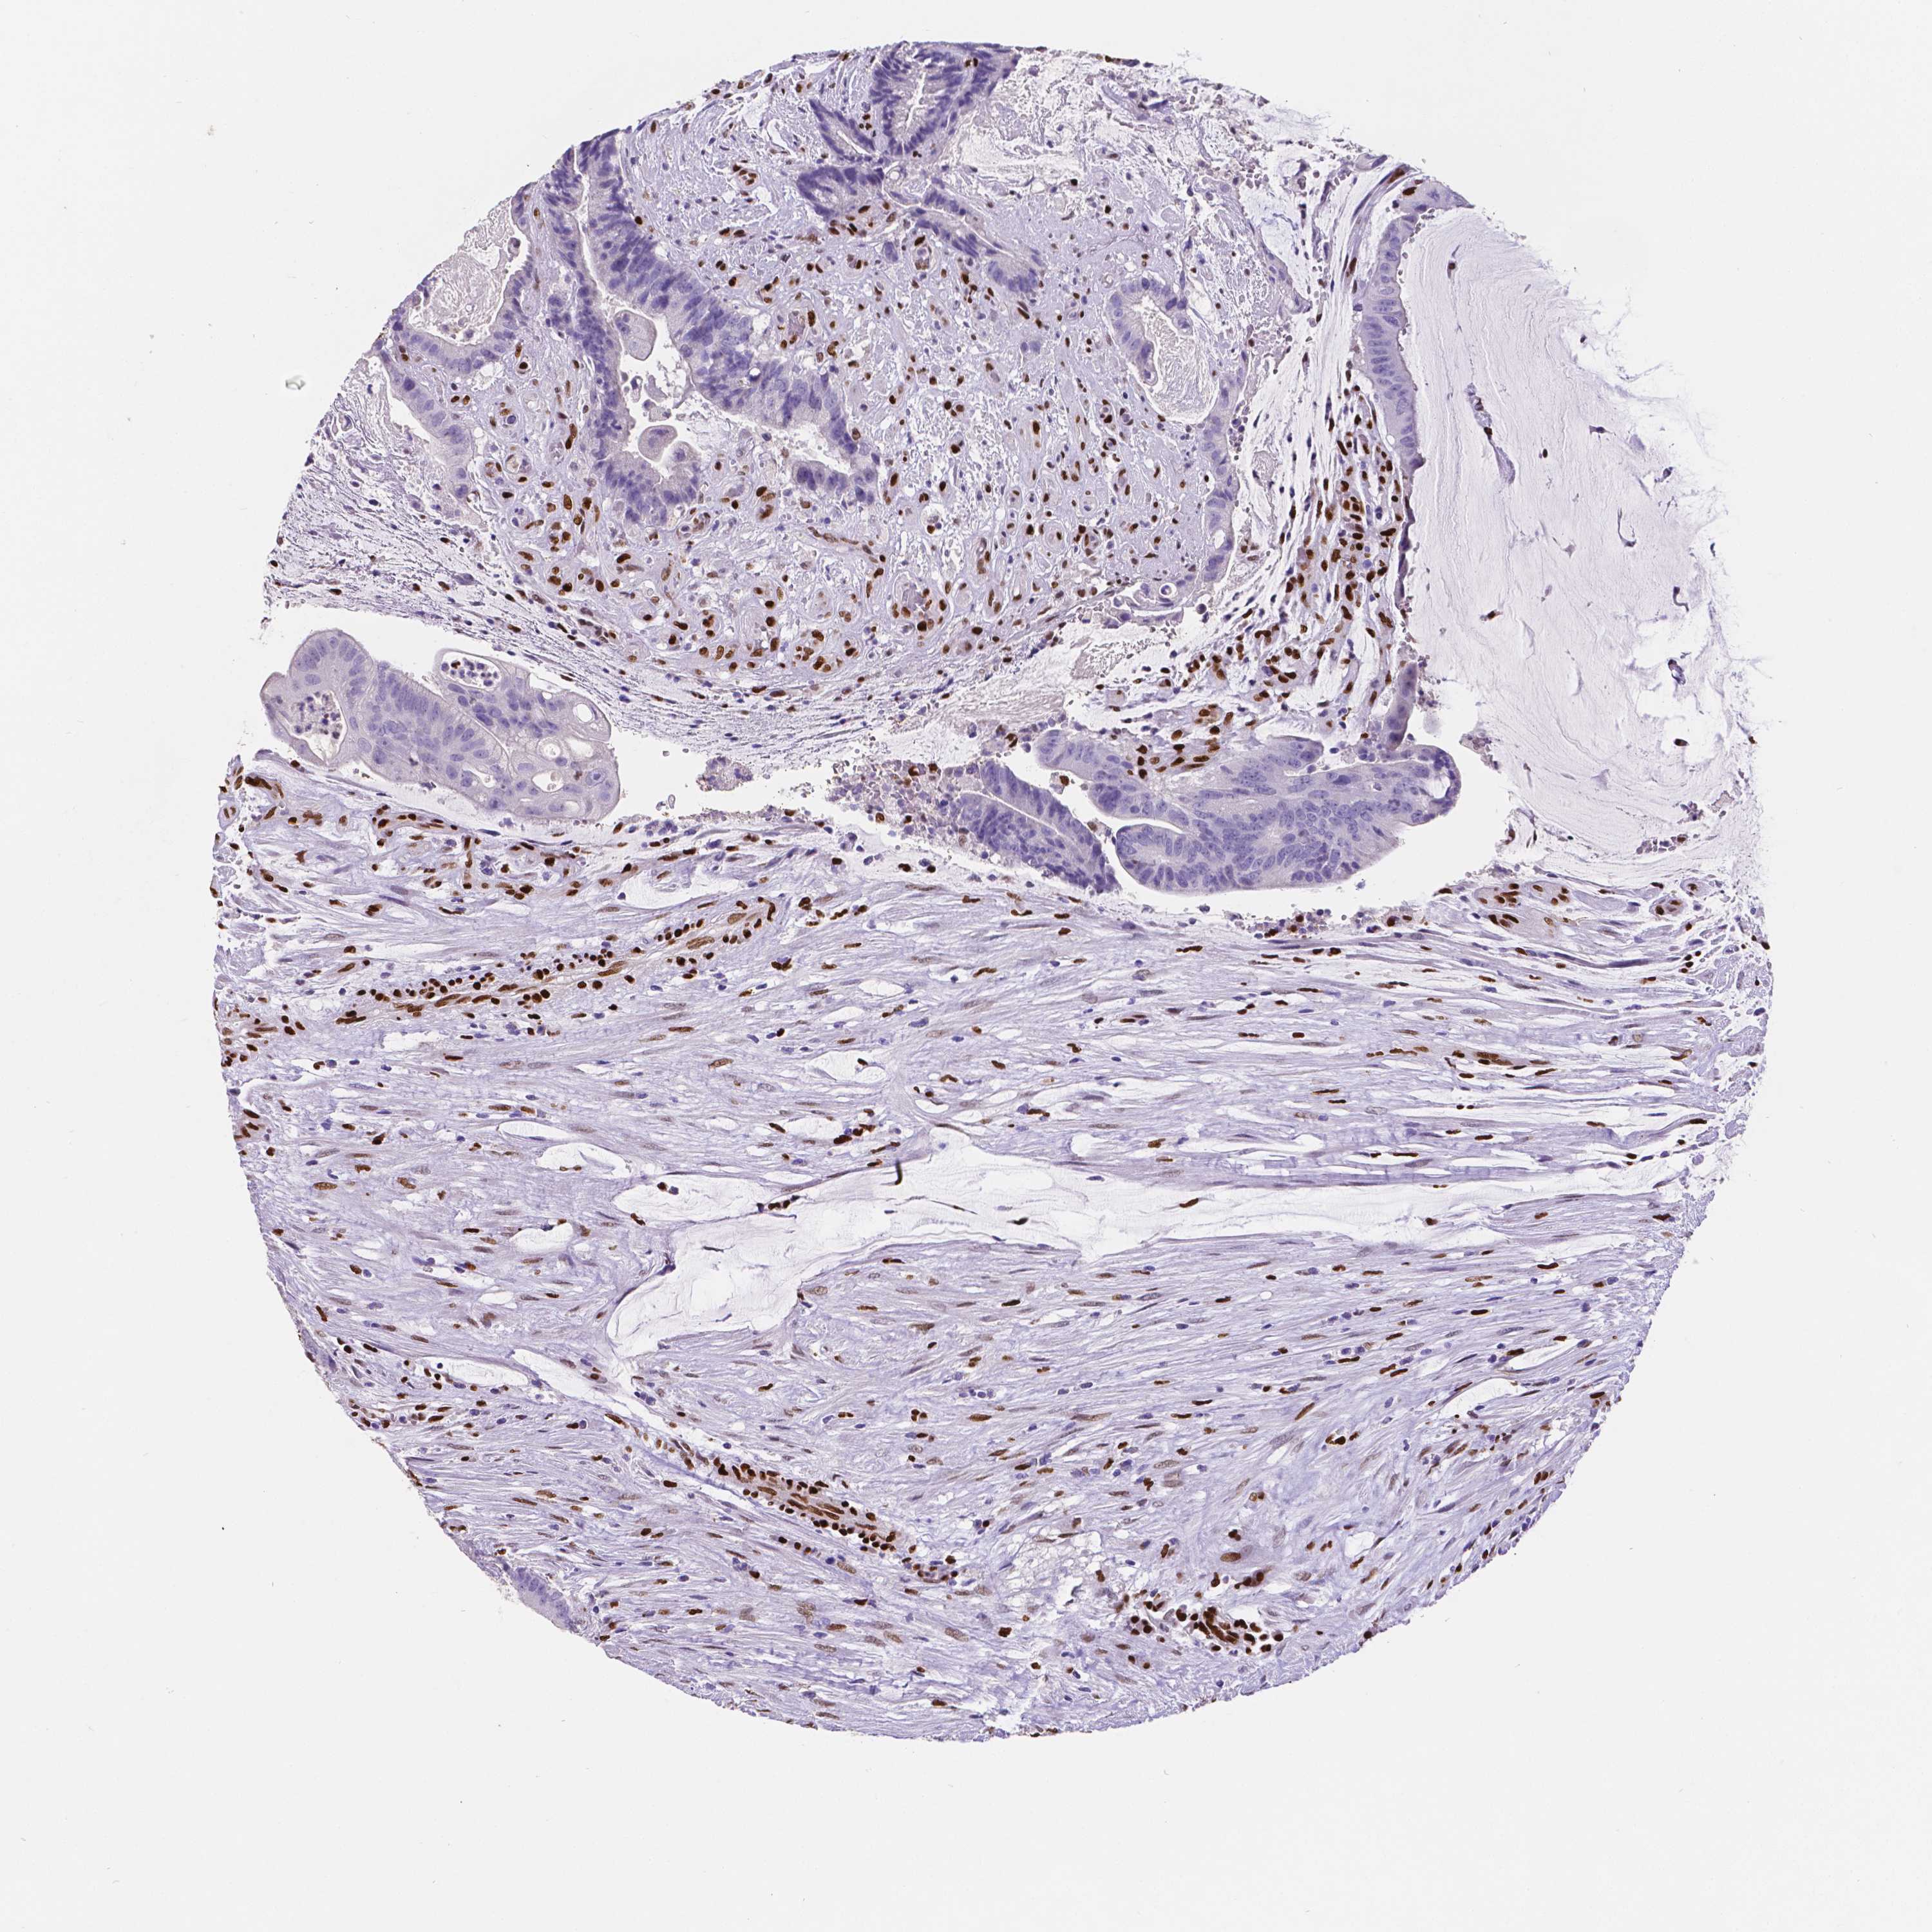

COAD TCGA COAD VALIDATION READ TCGA READ VALIDATION PROTEIN COAD CPTAC PROTEIN EXPRESSION

ANTIBODIES

AND

VALIDATION